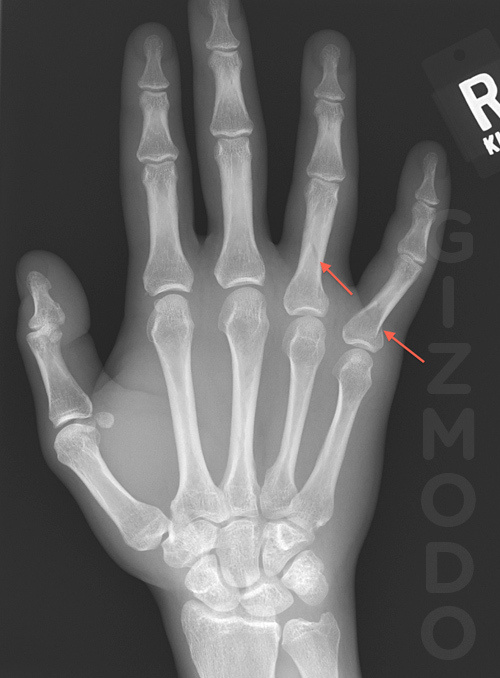

A physician has sent Gizmodo an x-ray, showing a patient that broke fingers in his hand playing God of War III. Apparently, the gamer got so caught up in playing, that he actually rolled over his hand with his knee. This caused two fingers in his hand to break. The physician wrote this for Gizmodo.

A physician has sent Gizmodo an x-ray, showing a patient that broke fingers in his hand playing God of War III. Apparently, the gamer got so caught up in playing, that he actually rolled over his hand with his knee. This caused two fingers in his hand to break. The physician wrote this for Gizmodo.

I had a patient who was so caught up in playing God of War III that he rolled over his hand with his knee and broke two fingers. The radiograph is attached (with his information omitted and arrows that point to the fractures). First time I’ve seen such an extreme gaming injury.